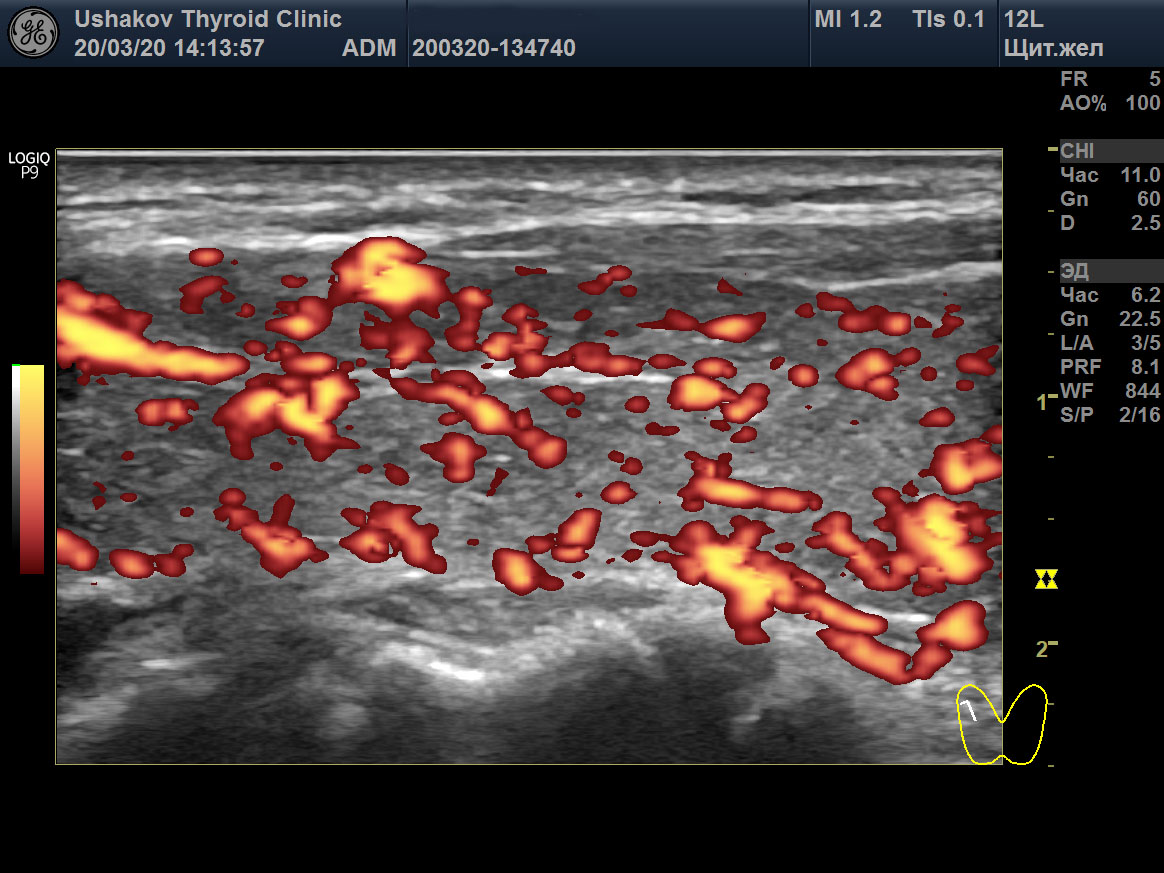

Пример такого случая представлен на

снимках ниже, где показаны две доли ЩЖ пациентки 31 года в режиме ЭДК и ПССК в системе верхних щитовидных артерий (ВЩА). Интенсивность кровотока при ЭДК усилена до значительной степени, а ПССК – до умеренно избыточной величины (норма 20-30 см/с [127]).

Рисунок 1 Левая и правая доли ЩЖ пациентки 31 года (поперечные и продольные проекции в режиме ЭДК; ПССК в режиме ЦДК), УЗИ 20.03.2020. Объём ЩЖ 9,1 мл (рост 170 см, масса 50 кг). Данные анализа крови от 18.03.2020: ТТГ 33,6 мЕд/л [0,4-4,0], Т4св. 6,7 пмоль/л [9,0-19,0], Т3св. 4,1 пмоль/л [3,0-5,6], АТТПО >1000 Ед/мл [<5,6], АТ-ТГ 368,8 Ед/мл [<18]. ПССК в системе ВЩА слева и справа 54 см/с. Концентрация йода в моче 200 мкг/л. Медикаменты не принимает продолжительный период.

Рисунок 1 продолжение

Рисунок 1 окончание |

В результате при обращении в нашу Клинику были выявлены признаки значительного перенапряжения ЩЖ по данным УЗИ в виде значительной интенсификации тиреоидного кровотока (

рис. 1). Эта избыточная стимуляция ЩЖ со стороны гипофиза (ТТГ 33,6 мЕд/) и периферической ВНС, тем не менее, сопровождалась